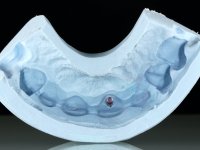

Segunda Fase

6 meses após a colocação da ponte, o paciente sofre um novo traumatismo comprometendo a viabilidade dos dentes 1.2 e 1.1. Foi realizada uma prótese removível acrílica para reabilitar provisoriamente o paciente enquanto foram extraídos os dentes 1.2 e 1.1 e foi colocado o implante no local do dente 1.1. Passados 3 meses foi realizada uma impressão ao implante colocado no 1.1 e simultaneamente foi feito um arrasto da ponte dos dentes 2.1 e 2.2. Para esse efeito no implante 2.1 foi utilizado um parafuso de uma peça de transferência. Dessa forma conseguiu-se impressionar corretamente a arquitetura gengival do sector antero-superior. O objetivo era simultaneamente impressionar corretamente esta zona e aproveitar a estrutura metálica desta ponte para confecionar a nova ponte de 4 elementos. Foi colocado um parafuso de cicatrização no implante 2.1 e foram acrescentados os dentes 2.1 e 2.2 na prótese removível. Com perícia laboratorial foi criada uma nova infraestrutura metálica de 4 elementos assente nos implantes 1.1 e 2.1 e com os elementos pônticos suspensos 1.2 e 2.2. No implante 2.1 manteve-se a conexão interna ao implante no implante 1.1 optou-se por uma peça intermédia facilitando a inserção da infraestrutura. A nova infraestrutura foi verificada em boca. Como pode ter havido alguma alteração da arquitetura gengival com a remoção da ponte e colocação do parafuso de cicatrização no 2.1, foi feita uma chave de silicone para permitir uma impressão de arrasto da infraestrutura metálica. Uma nova gengiva artificial foi realizada no modelo de trabalho de acordo com esta impressão de arrasto. Foi colocada cerâmica de tonalidade coronária e gengival. A peça protética foi aparafusada lentamente em boca para permitir uma adaptação dos tecidos moles. Após o correto assentamento e verificação imagiológica a ponte foi definitivamente apertada em boca e os orifícios de acesso obturados. Independentemente dos infortúnios que o paciente teve, pude ter a satisfação de o ver contente com esta reabilitação.